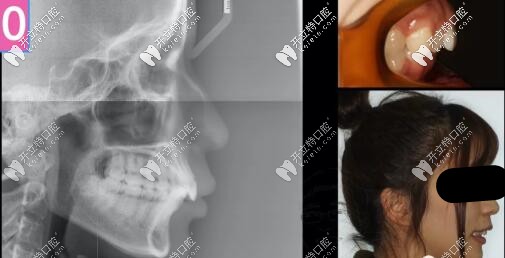

26歲女孩,來(lái)診主訴:嘴凸,大笑露牙齦,強(qiáng)烈訴求是解決嘴凸問(wèn)題。

二類(lèi)骨性齙牙正畸案例

側(cè)貌微凸,深覆合

右側(cè)磨牙尖牙關(guān)系II類(lèi),左側(cè)I類(lèi),

深覆合覆蓋5mm,下頜牙弓擁擠度5mm

骨性二類(lèi)凸嘴拔牙內(nèi)收案例

側(cè)位片提示:

骨性II類(lèi),均角,上前牙舌傾,下前牙唇傾前凸